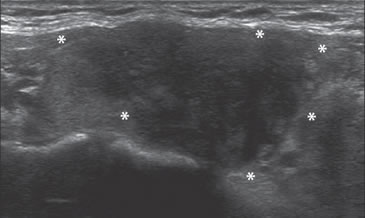

Figura 31. Área hipoecogénica en el lóbulo tiroideo aumentado de

volumen (asteriscos) que corresponde a un foco de tiroiditis de De

Quervain, que simula un tumor maligno.